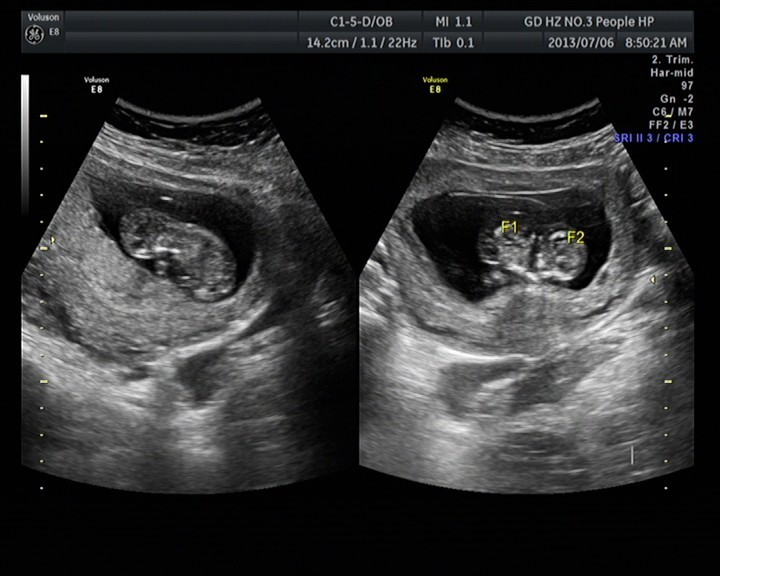

隨著環(huán)境污染日益嚴(yán)重,隨著各種地溝油的誕生,隨著各樣鎘大米的泛濫……我們的健康越來(lái)越受到威脅,很多疾病也隨之接踵而至,胎兒先天性疾病也越來(lái)越多見(jiàn)。7月6日,我院超聲科王瑤醫(yī)生在做胎兒產(chǎn)前NT篩查中發(fā)現(xiàn)一例孕約11周+的聯(lián)體雙胎。超聲所見(jiàn):增大的子宮內(nèi)可見(jiàn)聯(lián)體雙胎兒回聲,可見(jiàn)兩個(gè)胎頭不能分離,胸部及腹部融合,可見(jiàn)一個(gè)增大的心臟。

聯(lián)體嬰兒B超圖像